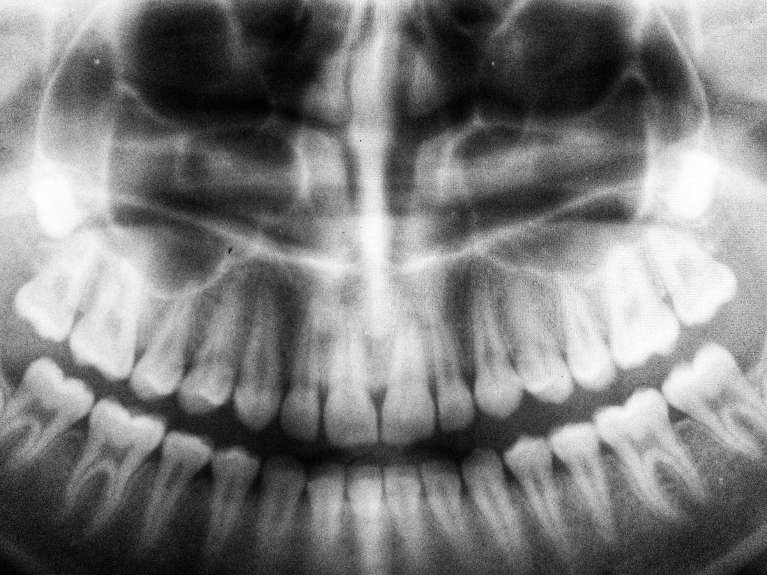

Panoramic X-Rays

When digital x-rays aren’t enough, we use panoramic x-rays to see your entire mouth in one image. A panoramic x-ray shows how your upper and lower teeth work together, giving us the information we need to identify impacted teeth, diagnose tumors or cysts, and plan orthodontic treatment, dental implant placement, and extractions.

Even if we don’t need a panoramic x-ray to diagnose your dental issues, we sometimes use them as an alternative for children or special needs patients who may require accommodations.